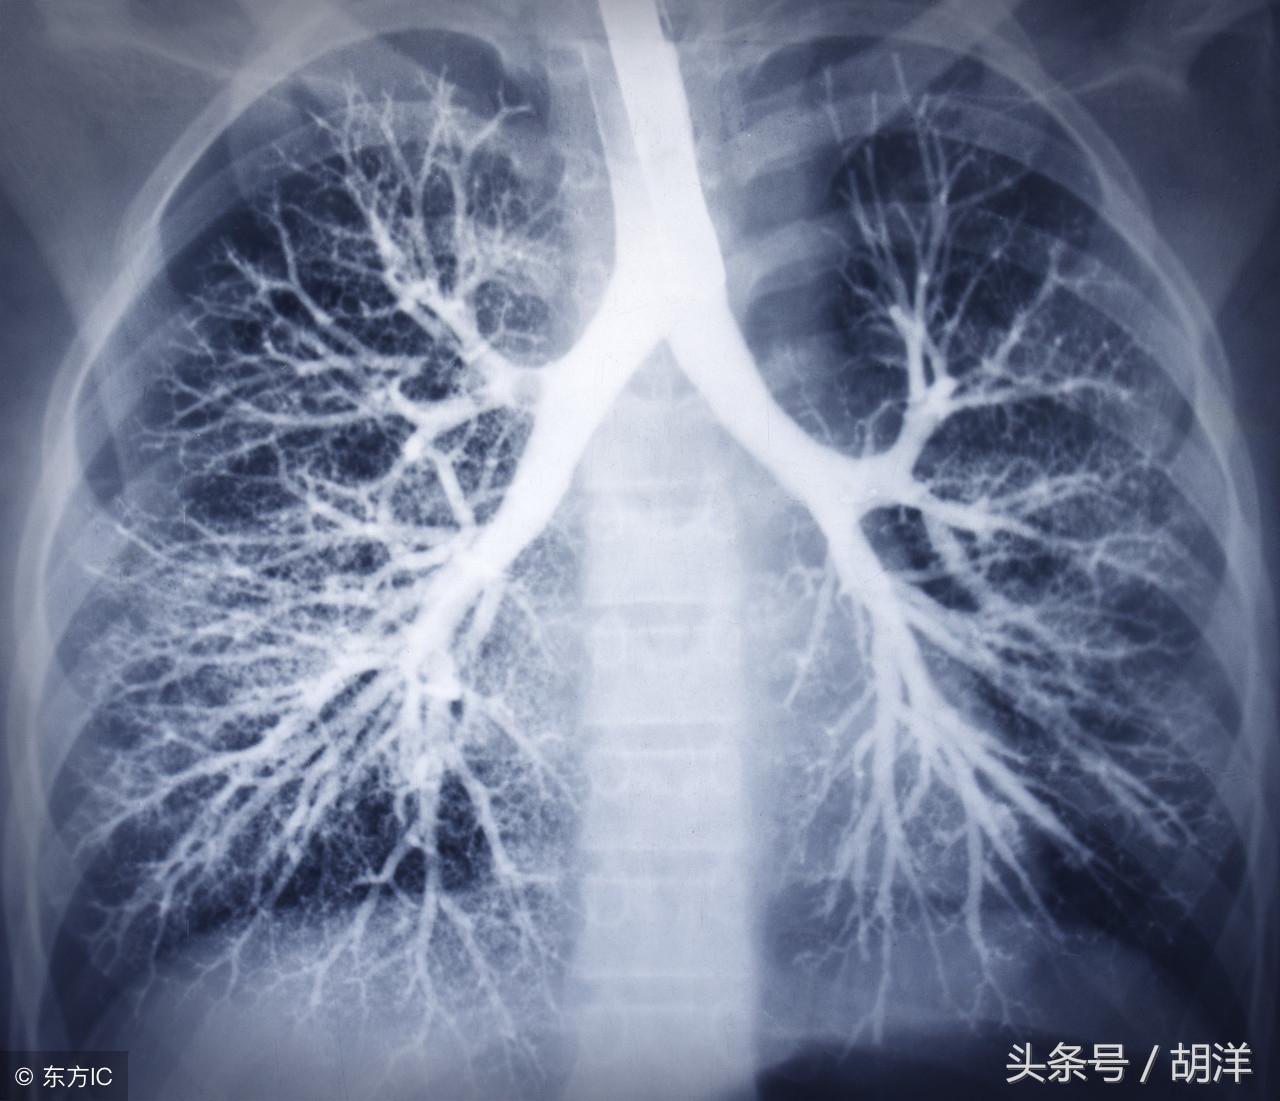

肺癌

肺癌也是较为常见的导致咯血的原因,恶性肿瘤细胞对于肺组织的侵蚀是其他疾病无法比拟的,几乎可以侵犯肺部正常组织中的所有结构,包括血管,另外,肺癌癌肿由于生长过快,其表面的细胞可能会因为得不到充足的血液供应而坏死,这样的坏死很容易产生渗血,是引起痰中带血的常见原因。